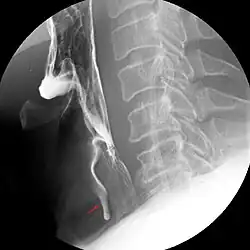

Fremdkörperaspiration

Eine Fremdkörperaspiration zeigt sich etwa daran, dass der Patient plötzlich nicht mehr atmen, sprechen und husten kann.[2] Am häufigsten kommt die Fremdkörperaspiration bei Kindern vor. Hauptsächlich betroffen sind ältere Säuglinge und Kleinkinder im Alter von ein bis vier Jahren aufgrund ihrer generellen Tendenz, Gegenstände in den Mund zu nehmen oder in unruhiger Situation etwas zu essen, was eine glatte Oberfläche hat.[3] Die am häufigsten von Kindern aspirierten Fremdkörper sind Erdnüsse, aber auch Bonbons oder kleine Spielzeugteile.[4] Jungen sind dabei mit bis zu 65 % überrepräsentiert. Auch bei Erwachsenen treten Aspirationen von Fremdkörpern auf, beispielsweise wenn jemand bei handwerklichen Arbeiten Nägel oder Schrauben mit dem Mund festhält, dann erschrickt und plötzlich stark einatmet.

Aufmerksam sollten Anwesende werden, wenn es bei einer Person zu einer plötzlichen Hustenattacke kommt, die mit Atemnot einhergehen kann, aber nicht muss. Eine radiologische Untersuchung mittels Röntgen-Thoraxübersichtsaufnahme, Röntgen-Thoraxaufnahme in Exspiration oder einer Durchleuchtung sind erste diagnostische Maßnahmen. Eine Szintigraphie ist eine weitere Möglichkeit. Die Krypton-81-m-Ventilationsszintigraphie hat eine besonders hohe Detektionsrate. Schließlich sollte eine Bronchoskopie neben der diagnostischen Klärung auch den therapeutischen Erfolg bringen.